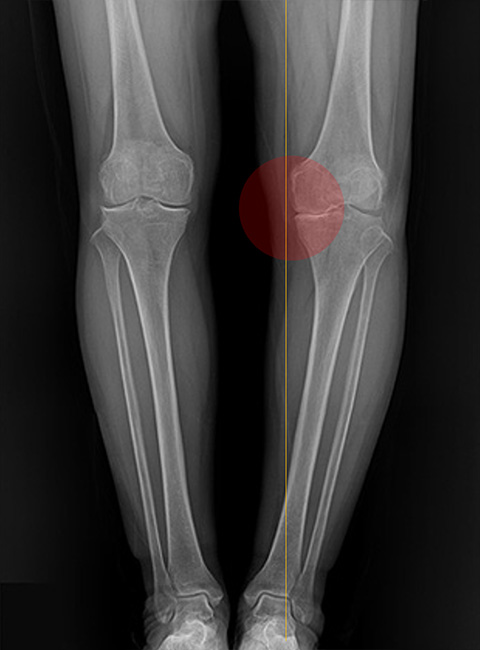

Before

O자 휜 다리와 내측 무릎 관절염으로 무릎 안쪽 간격이 좁아져 서로 충돌하는 상태

-

After

체중 부하를 무릎 바깥쪽으로 이동시켜 좁아졌던 무릎 안쪽 간격이 넓어지고, 다리 모양도 일자로 교정된 상태